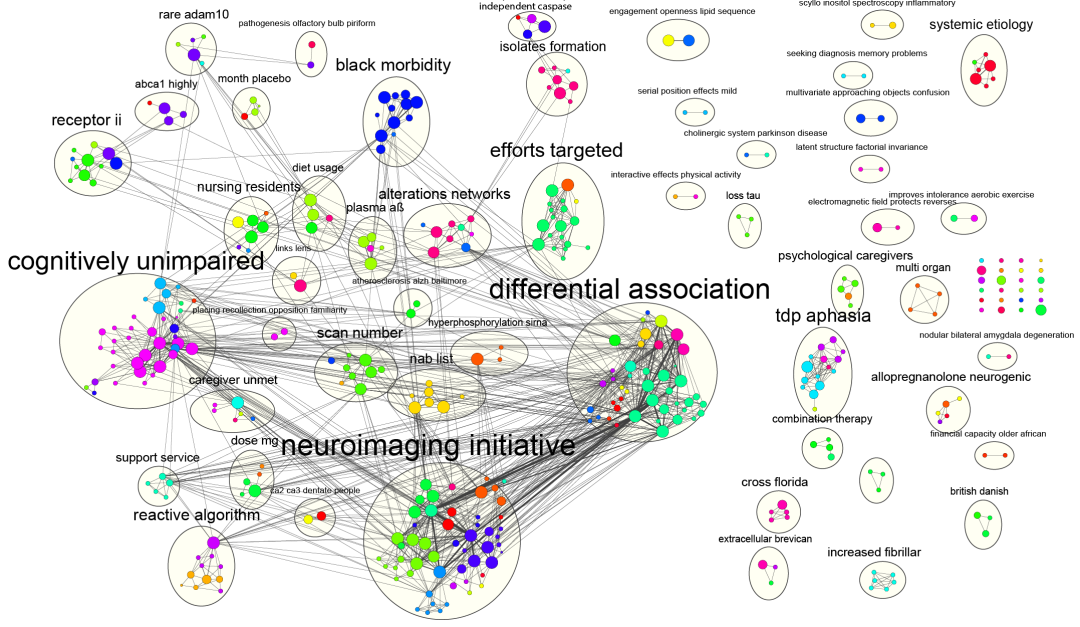

滑动查看更多 点击查看大图

期刊封面图设计

滑动查看更多 点击查看大图

论文图表排版

滑动查看更多 点击查看大图

论文图表美化

滑动查看更多 点击查看大图

数据分析与作图

滑动查看更多 点击查看大图